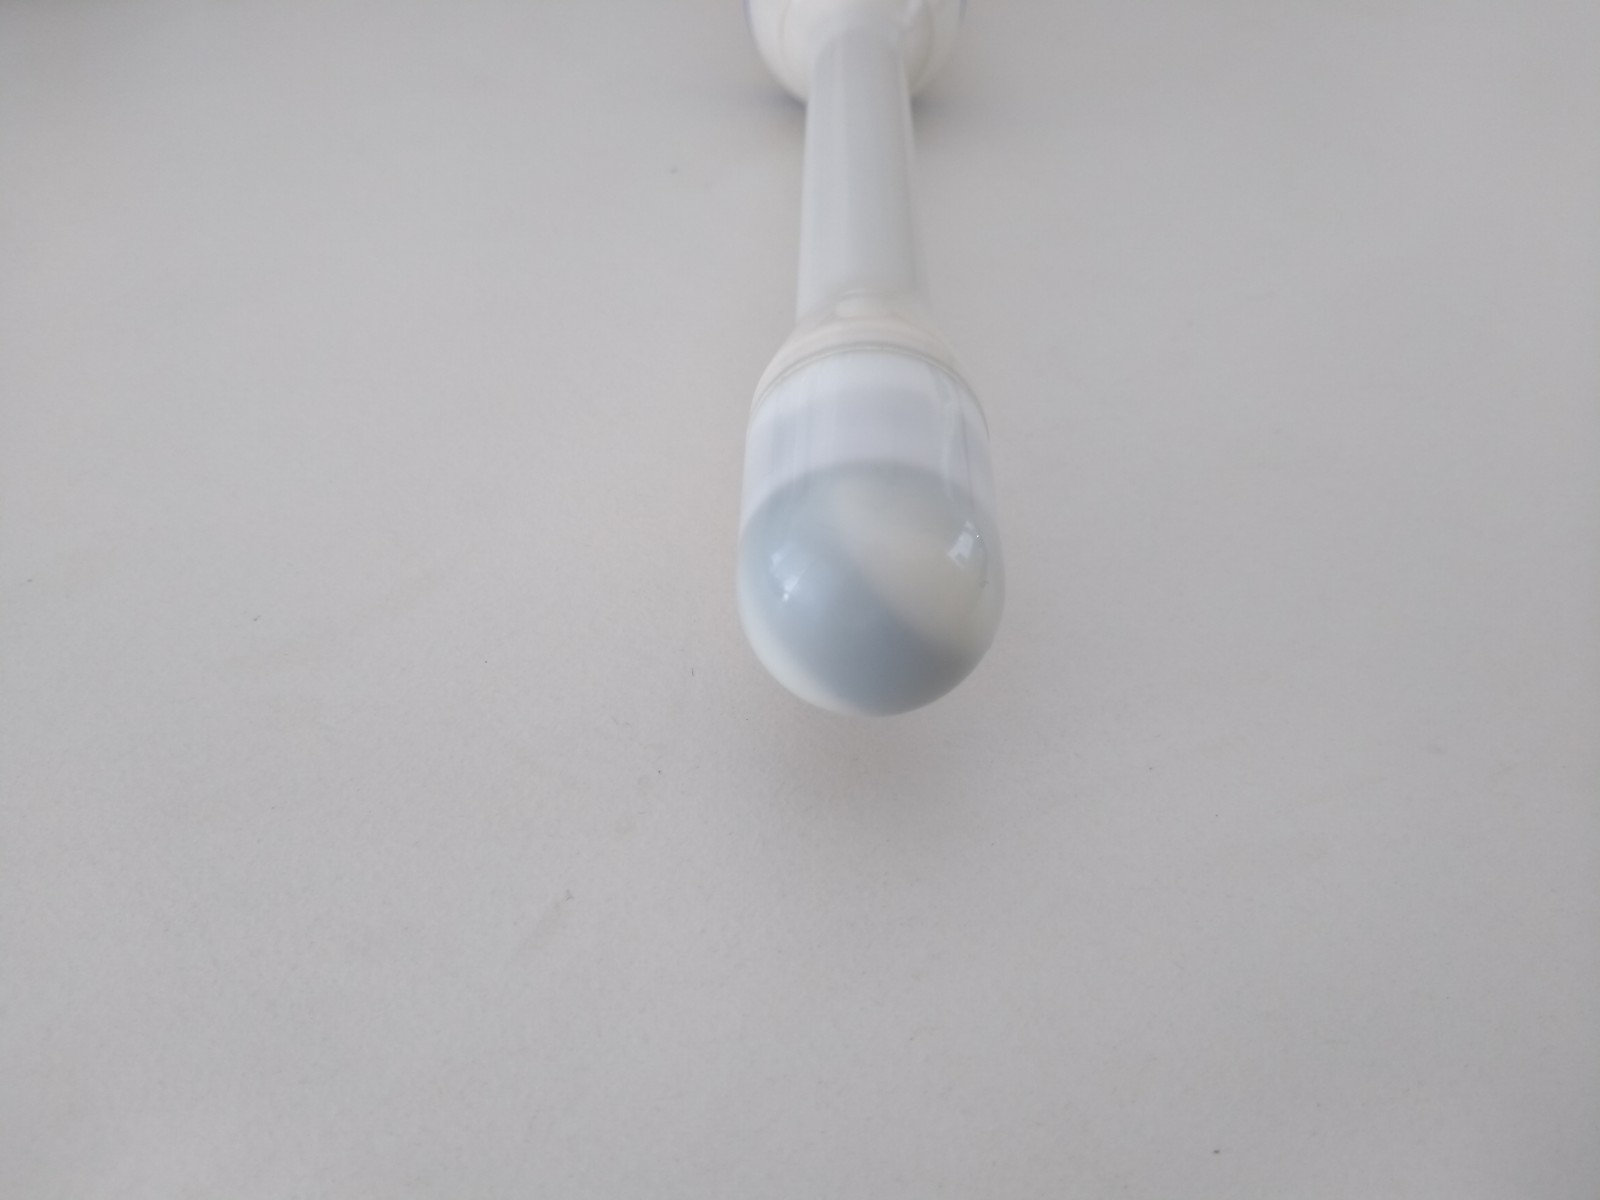

Aloka Vaginal ASU-1003 3D/4D

Aloka ASU-1003 3D/4D Vaginal – ProSound

Frequency Range: 9 – 3 MHz

Scan Width: 9 mm Radius

Scan Angle: 163° FOV

Prosound Connector

Aloka ASU-1003 3D/4D Vaginal – ProSound for Volume Obstetric and Gynecology